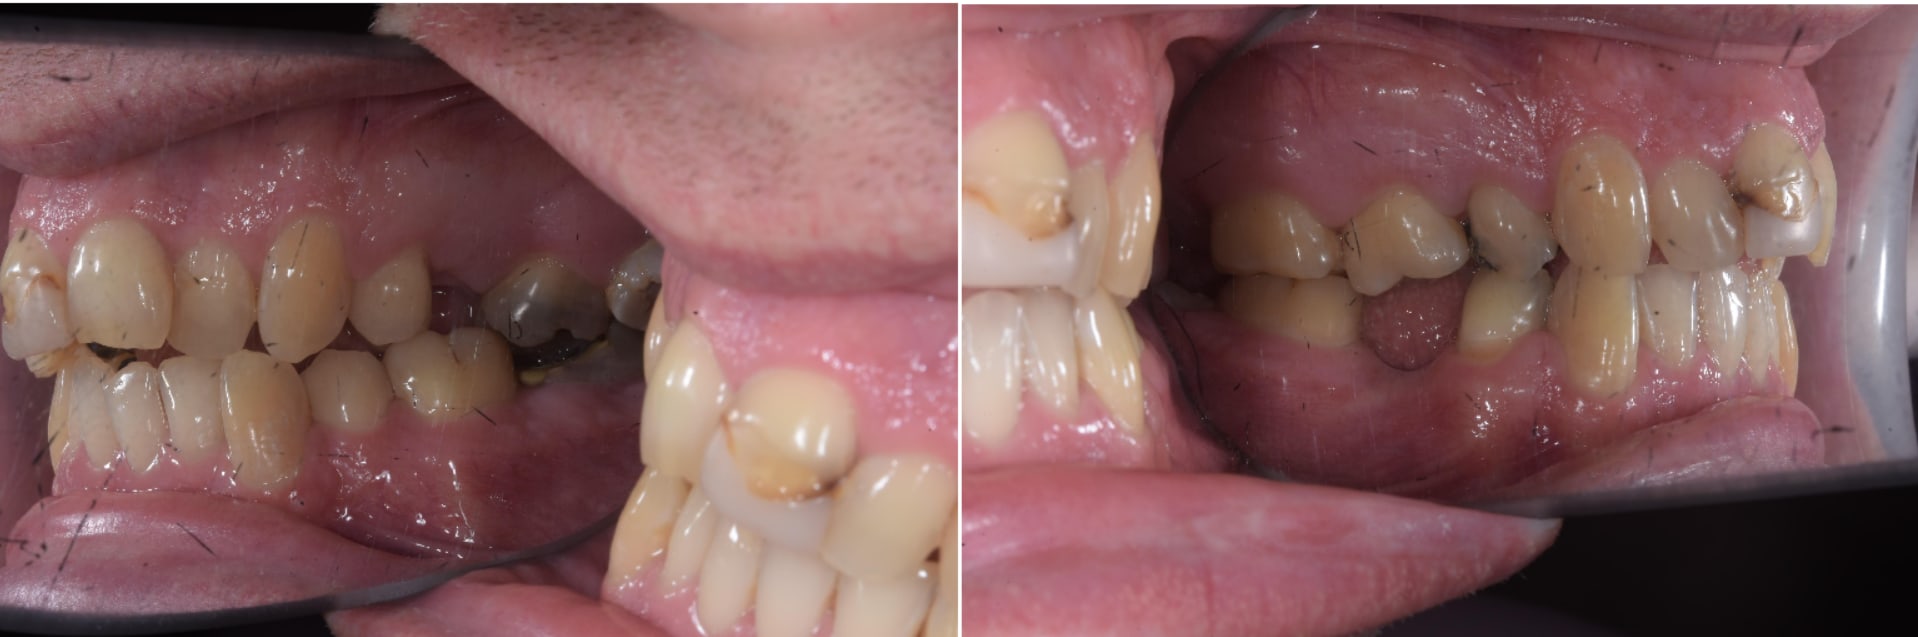

Rudy 12 ans et 3 mois.

Comme d'habitude motif de consultation douleur.

Pour commencer ce type de situation c'est ultra fréquent dans ma pratique privée, avec les expats aussi bien que les Cambodgiens. Enfant de famille " modeste " , friqué ou même de dentiste, donc ça ne me choque pas tant que ça.

Au niveau du traitement c'est simple et ça ne rallonge le traitement de 6 mois grand max sans avoir besoin d'acte supplémentaire ( comme des minivisses ).

Oui, cela fonctionne dans la cadre de la CMu, mais aujourd'hui comme le rappelle lardon c'est l'extraction d'une dent qui peut être conservée autrement.

Donc globalement, tu joues les choses à 2 pour pouvoir justifier plus tard si le patient ne fait pas les soins intégralement qu'il était correctement informé des conséquences du retrait de cette dent.